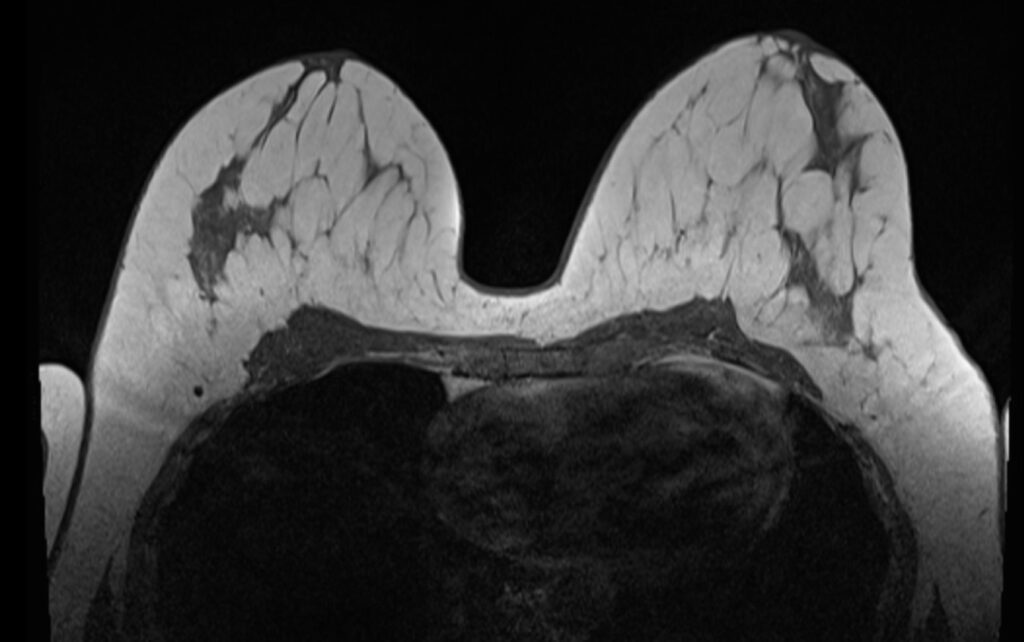

Konnten die klinische Untersuchung, die Mammographie und die Mammasonographie keine eindeutigen Ergebnisse liefern, kann als Ergänzung die Magnetresonanztomographie (MRT) herangezogen werden. Die hohe räumliche Auslösung kann dabei helfen, bereits sehr kleine Herde in der Brust erkennbar zu machen.

Hier zu sehen sind Bilder einer Brust MRT / Mamma MRT.